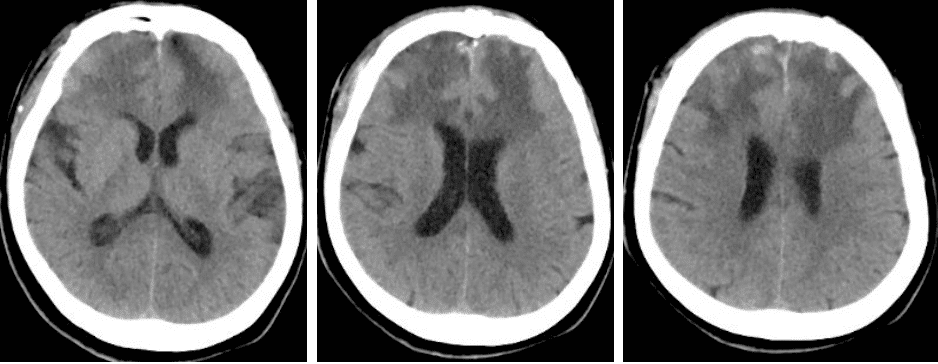

头CT(术后 2023-12-18)颅内占位切除术后,额骨见骨瓣影,额部头皮软组织肿胀。双额叶见斑片状不均匀密度影,边界模糊,呈高低混杂密度,大脑镰及额叶部分脑沟密度增高。脑室及脑池系统无扩张。双侧脑沟裂无增宽、加深,中线结构居中。